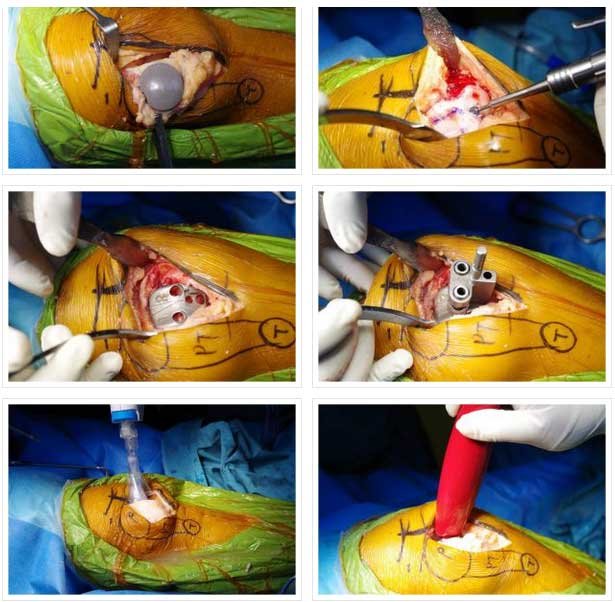

PATELLOFEMORAL

- PATELLA REPLACED WITH POLYTHYLENE INSERT

- TROCHLEA WITH UNCONSTRAINED METAL

- INLAY AND ONLAY TECHNIQUE: INLAY MY PREFERRED- LAZY

- PATELLAR TRACKING TO BE CLOSELY EXAMINED BEFORE SURGERY, MOST REQUIRE LATERAL RELEASE.

PATELLOFEMORAL ARTHRITIS IN- 40 YEAR OLD FEMALE

PATELLOFEMORAL REPLACEMENT-POSTOP